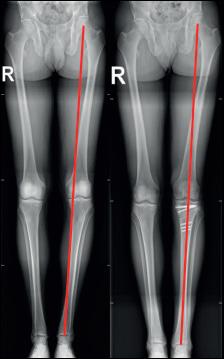

Bij een neutraal alignement (= recht been) gaat ongeveer 70% van de druk door het mediale compartiment en slechts 30% door het laterale. Bij een O-benen (varus) loopt dit vanaf 3-5° varus op tot 100% mediaal, bij X-benen is er meer druk lateraal (foto 1).

Foto 1 Alignement onderste lidmaat. Bij een neutraal of normaal alignement, wordt ongeveer 70% van het lichaams gewicht door het mediale compartiment gedragen. Bij varus (O-benen) is dit 100%. Bij valgus (X-benen) is de druk in het lateraal compartiment verhoogd.

Daarom zal artrose bij een patiënt met onderliggend een varusafwijking zich quasi altijd bevinden thv het mediale compartiment. Door de artrose, wordt de kraakbeenlaag dunner in het mediale compartiment, waardoor het been nog meer in varus kantelt en de druk op het mediaal compartiment zal verder verhogen. Daarom wordt dit ook een variserende gonartrose genoemd. Bij een valgus alignement zal de artrose het vaakst optreden in het lateraal compartiment met hierdoor een progressieve X-stand van het been. Dit wordt dan een valgiserende gonartrose genoemd.